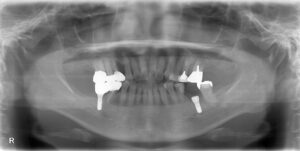

画面向かって右下に1本手術行いました。

画面向かって左下も以前当院で行ったインプラントです。

こちらの患者様は、以前インプラントを検討しておられましたが、できないと断られた経緯があり、当院で精密検査行い、インプラント手術が可能と判断でき、セラミック装着したレントゲン写真です。